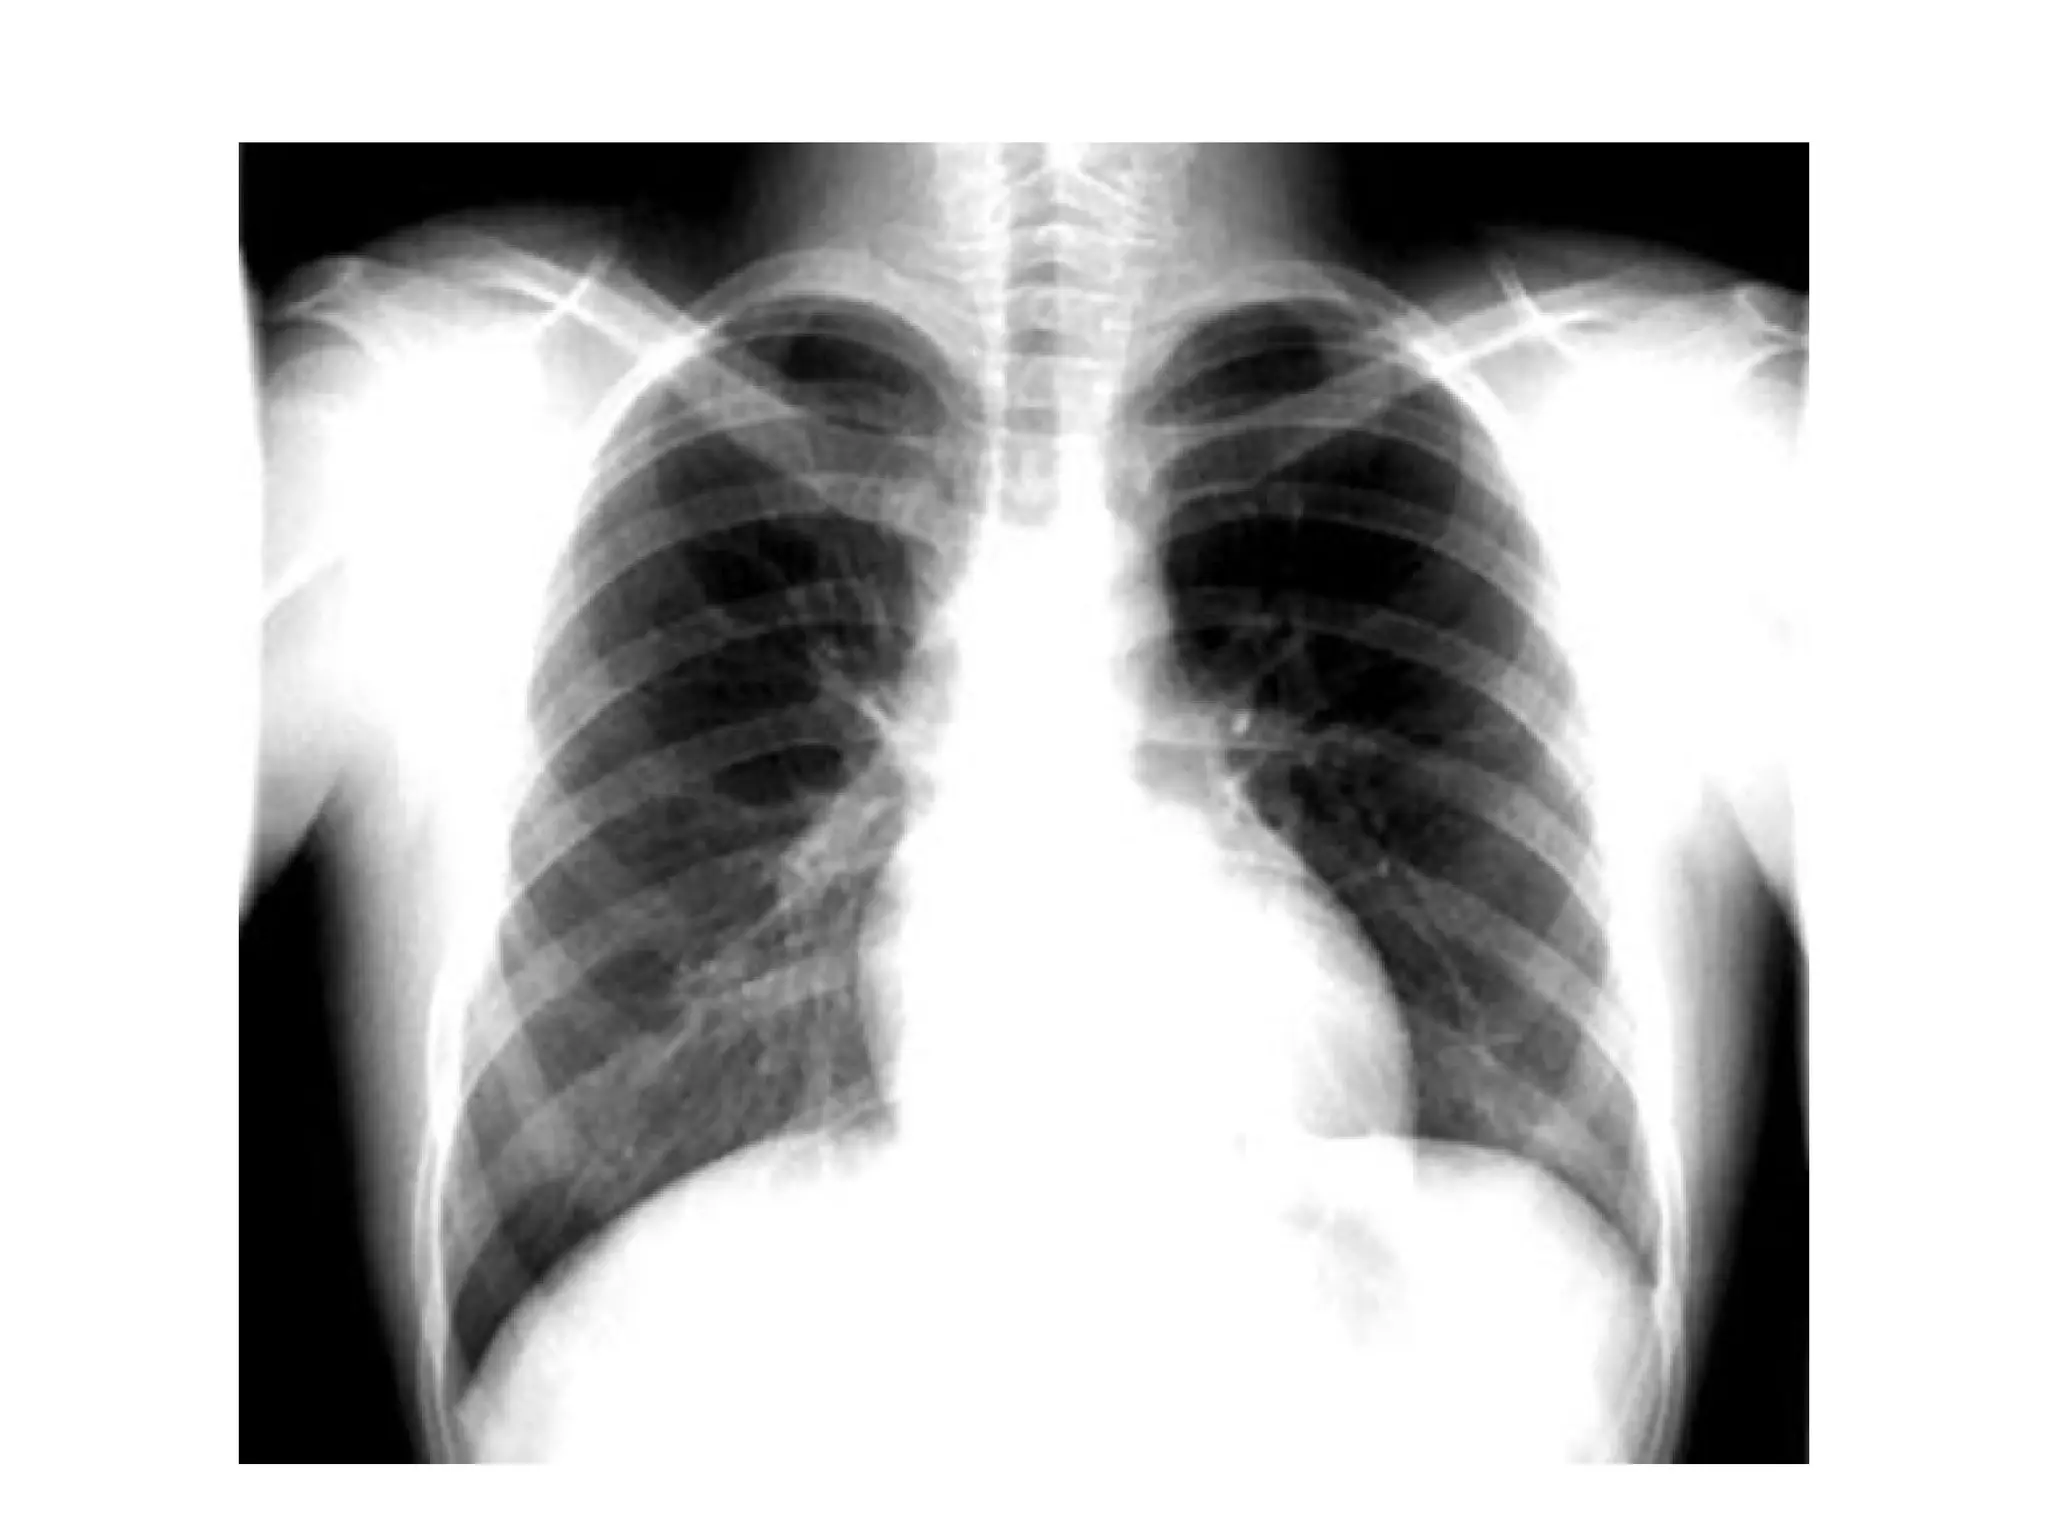

DIJAGNOSTIČKE PROCEDUREDIJAGNOSTIČKE PROCEDURE

• ELEKTROKARDIOGRAM , EKGELEKTROKARDIOGRAM , EKG

• RENDGENSKI SNIMAK SRCA i PLUĆARENDGENSKI SNIMAK SRCA i PLUĆA

Rtg pluća i srca – normalan nalazRtg pluća i srca – normalan nalaz

D’ D G G’ α Tr2Tr1 TrTh RA VCS (Asc.A) T A PA A.AL LV Rtg pluća i srca – normalan nalazRtg pluća i srca – normalan nalaz